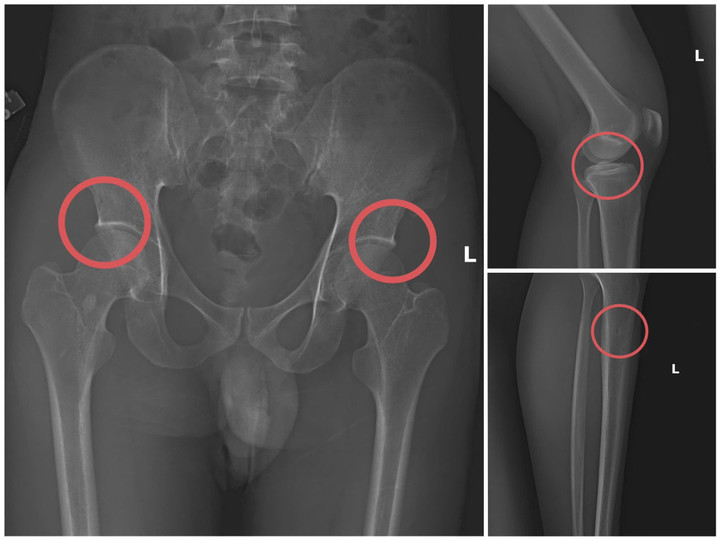

Bản phim chụp XQ một số tổn thương xương do đối tượng tạo ra. (Ảnh: Công an tỉnh Phú Thọ).

Đáng chú ý, Châu trực tiếp thực hiện hành vi tiêm thuốc mê, rồi dùng kim tiêm, búa... để tác động vào xương người mua bảo hiểm, tạo nên các vết nứt, vỡ xương tương tự tai nạn thật.

Lợi dụng thời gian dài công tác trong ngành Y tế và am hiểu sâu cấu tạo xương – khớp, cũng như cơ chế chi trả bảo hiểm đối với các thương tích gãy xương giá trị cao, Châu dựng lên một quy trình trục lợi bài bản, từ việc vận động mua bảo hiểm, tổ chức gây thương tích, đến hợp thức hóa hồ sơ bệnh án để chiếm đoạt tiền của các công ty bảo hiểm.